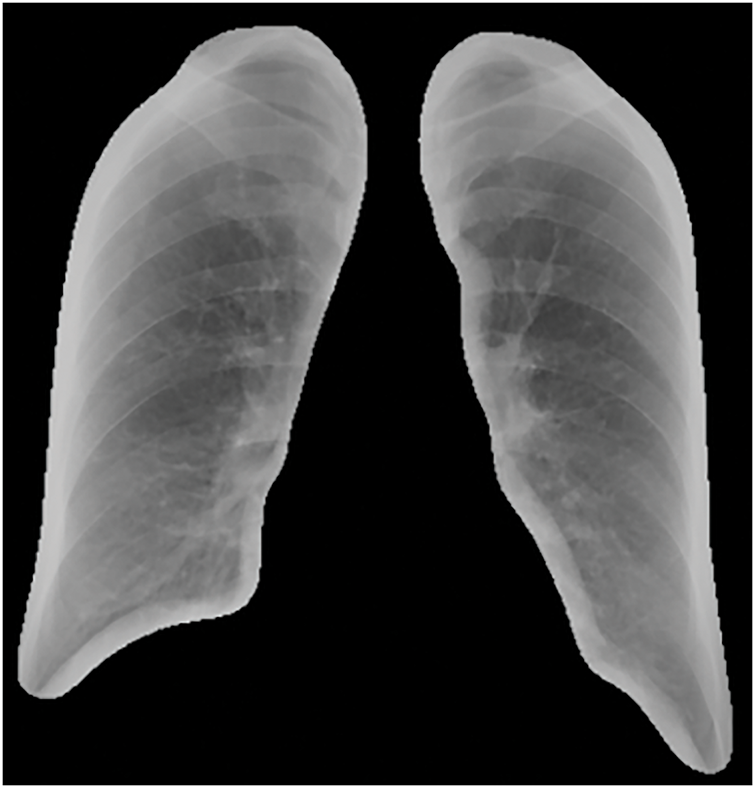

The predicted masks obtained through the U-Net model were applied to the original DR images to extract lung regions, achieving an accuracy of 97%. Initially, the glob library was used to batch-read the original and predicted image files. Each predicted image was converted to grayscale and then binarized by thresholding, retaining only parts with grayscale values above 200, considering these as lung regions. Subsequently, the mask was resized to match the original image dimensions to ensure precise coverage. By applying this mask, the lung regions in the original images were extracted. As shown in Figs. 2 and 3, this is an example of the image after lung segmentation using U-Net.

Figure 3: Lung segmentation image